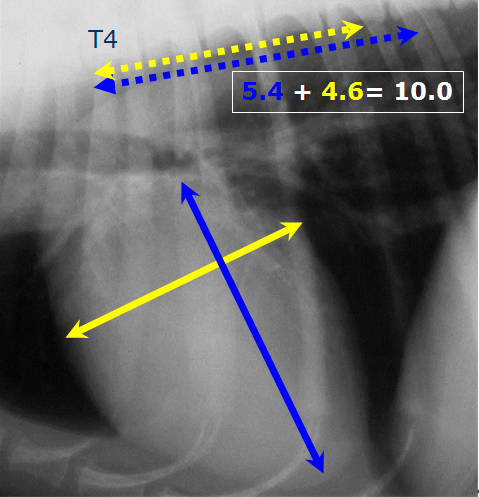

What is the vertebral heart score?

Add the no. of vertebrae

Suggested normal range

= 8.5 – 10.5

Breed specific values available

•Normal ranges differ between breed so always refer to this